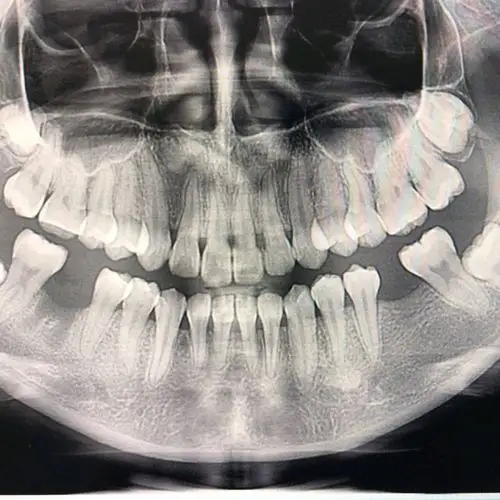

种牙牙片欣赏

种植牙真的不是老年人的专利~我来种牙了~一颗大牙蛀_圈子-新氧美容

我的种植牙日记机械维修工程师的渡江口腔种植修复之路